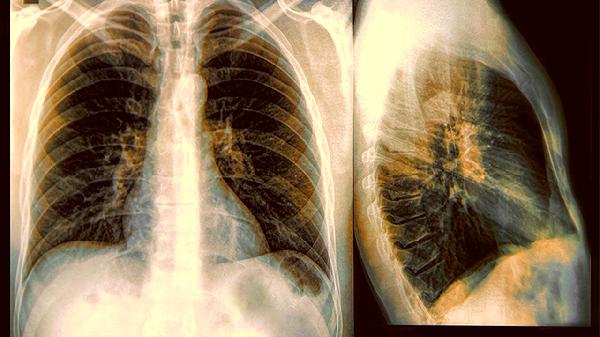

3.检查性价比之选

胸片能发现多数肺部重大问题,辐射量仅相当于3天自然本底辐射。担心辐射拒绝检查,可能错过火灾预警器;但也不必直接要求做增强CT,医生会根据风险分层选择检查。